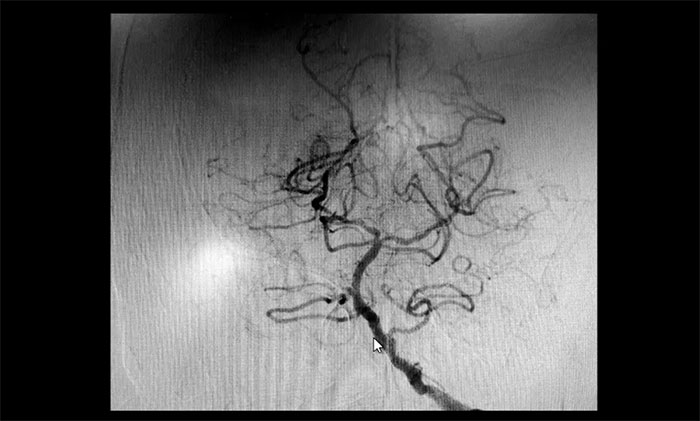

颈内动脉狭窄可分为轻度(<50%),中度(50%~69%)和重度(70%~99%),椎动脉狭窄的判别标准与之相仿。DSA检查示:患者双侧颈内动脉及左侧椎动脉存在重度狭窄,狭窄程度达到甚至超过90%,病情十分严重,遂立即收治入院。

▲ 双侧颈内动脉及左侧椎动脉重度狭窄

▲ 术后,左侧颈内动脉狭窄明显改善